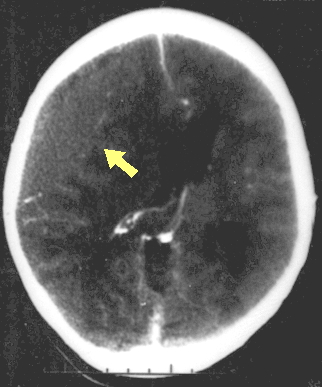

외상성 뇌손상(TBI)의 진단은 병변의 상황과 임상 증거, 특히 신경학적 검사 결과를 바탕으로 의심된다.[162] 신경 영상 검사는 진단 및 예후를 결정하고 적절한 치료법을 결정하는 데 중요한 보조 수단으로 활용된다.[165] 또한, DSM-5는 외상성 뇌손상과 관련된 정신과적 후유증을 진단하는 데 사용될 수 있다.[69][70][71]

신경 영상 검사는 외상성 뇌손상의 진단 및 예후를 결정하고 적절한 치료법을 결정하는 데 도움이 된다.[165]

응급 상황에서는 컴퓨터 단층촬영(CT)이 가장 선호되는 방사선 검사다. 신속하고 정확하며 널리 사용 가능하기 때문이다.[73] 손상이 진행되었는지 확인하기 위해 추후 CT 촬영을 실시할 수도 있다.[193]

국소 손상의 한 종류인 뇌좌상은 뇌 조직이 찢어지거나 절단될 때 발생한다.[173] 특히 눈 위의 두개골 안쪽 뼈 돌출부 때문에 전전두엽 피질에서 흔하게 발생한다.[24] 뇌좌창은 뇌 조직에 멍이 드는 것으로, 혈액이 조직과 섞이는 상태를 말한다.[162] 반면 두개내 출혈은 혈액이 뇌 조직과 섞이지 않고 고이는 출혈을 의미한다.[173]

혈종 역시 국소 병변으로, 출혈로 인해 뇌 안이나 주변에 피가 고이는 것을 말한다.[7] 뇌 조직 자체에 출혈이 생기는 뇌내 출혈은 뇌막내성 병변이다. 뇌막외성 병변에는 다음과 같은 종류가 있다.[30]